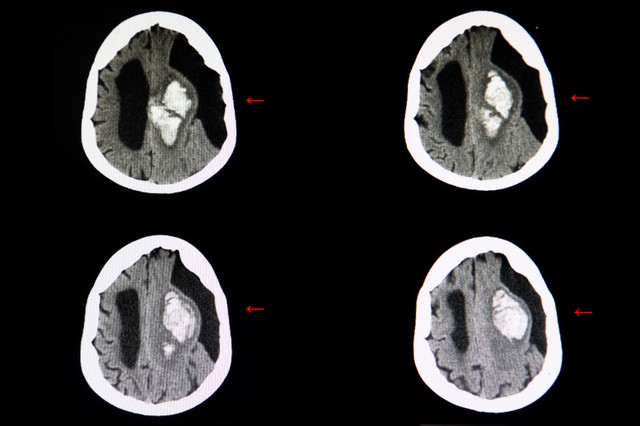

Subarachnoideális ciszta tünetei, vizsgálata és kezelése

A subarachnoideális ciszta agy-gerincvelői folyadékkal telt hólyag, ami kialakulhat az agy és a koponyaalap között, vagy az arachnoideális hártyán. A legtöbb eset a gyermekkorban alakul ki, habár néha a felnőttkorban is előfordulhat. Arachnoideális ciszták férfiakban gyakrabban fordulnak elő.